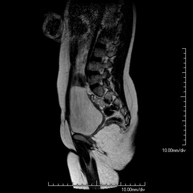

Prova diagnòstica no invasiva que consisteix en l'obtenció d'imatges d'alta definició anatòmica de la columna lumbar i sacre mitjançant l'ús d'un camp electromagnètic i ones de ràdio (amb un emissor i un receptor). No utilitza radiació ionitzant. Indicacions: traumatismes, ciàtica, hèrnies discals, tumors, infeccions - RM Mielografia

Prova diagnòstica no invasiva que consisteix en l'obtenció d'imatges d'alta definició anatòmica de la columna lumbar i sacre mitjançant l'ús d'un camp electromagnètic i ones de ràdio (amb un emissor i un receptor). No utilitza radiació ionitzant. Indicacions: traumatismes, ciàtica, hèrnies discals, tumors i infeccions. - RM de Sacre-còccix